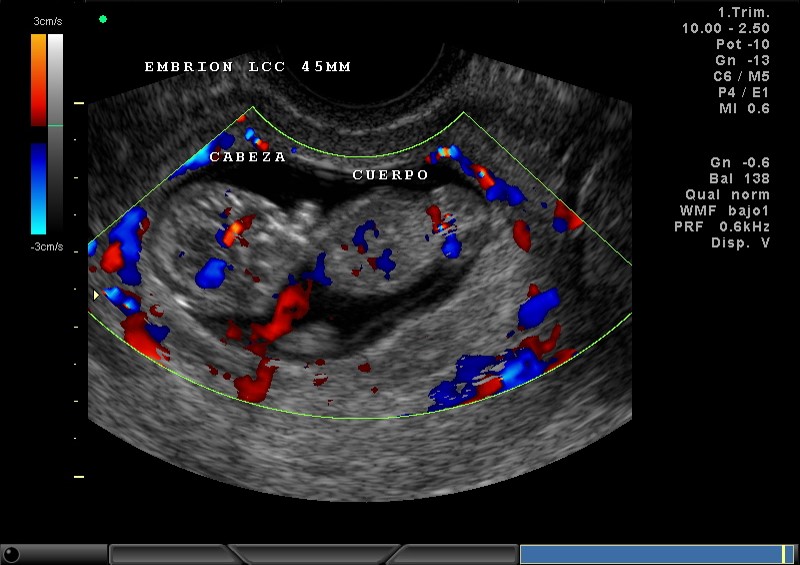

2D Y COLOR CABEZA, CUERPO, VASOS